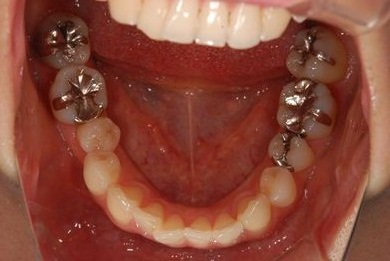

| 性別/年齢 | 女性 / 31歳 | ||||||||||||||||||||||||||||||||

| 主訴 | 前歯の歯茎が黒ずんでいるので、改善したい。 | ||||||||||||||||||||||||||||||||

| 治療方針 | 上顎前歯、メタルボンドセラミッククラウンからオールセラミッククラウンにする事で、審美的回復を行う。 | ||||||||||||||||||||||||||||||||

| 治療内容 | CAD/CAMオールセラミッククラウン2本(セラミック用土台2本) | ||||||||||||||||||||||||||||||||

| 総治療費 | 142,800円 | ||||||||||||||||||||||||||||||||

| 治療期間 | 2ヶ月 |